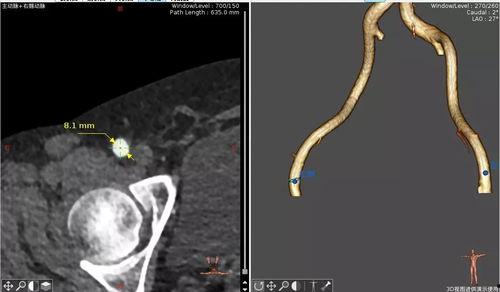

你有没有想过,医生在进行成人股动脉穿刺时,是如何精准定位穿刺点的呢?今天,就让我带你一探究竟,揭开这个神秘过程的神秘面纱!一、股动脉穿刺点定位的重要性首先,得说说股动脉穿刺点定位的重要性。这可不是闹着玩的,它关系到手...